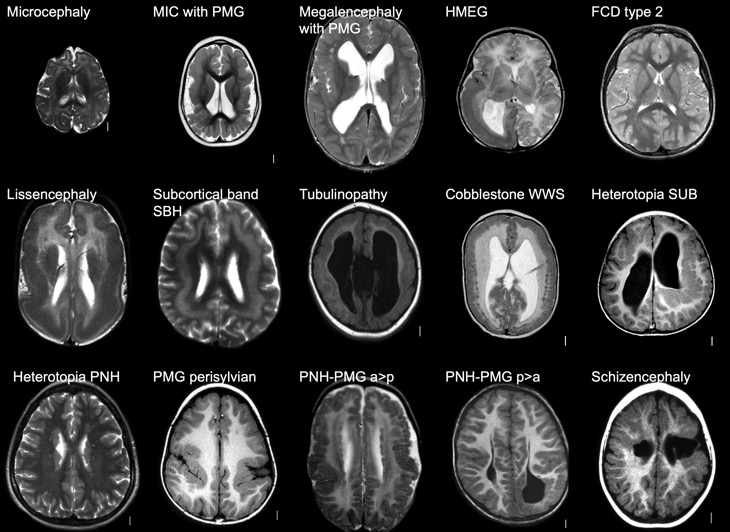

Troubles de la maturation et de la migration du cerveau pédiatrique.